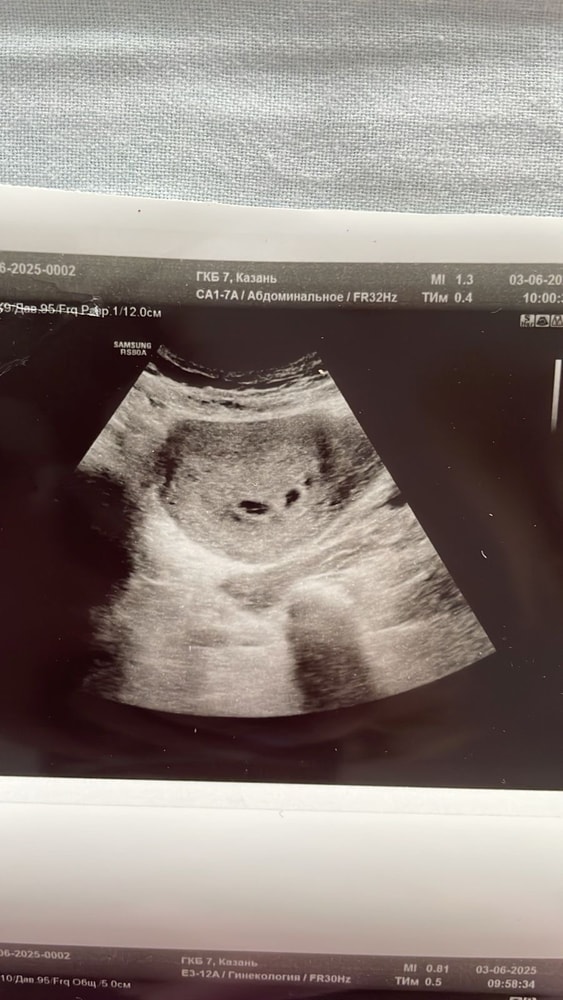

Узи

Сегодня была у своего гинеколога, сделали УЗИ, снова увидела своих бриллиантиков🥰🥰 следующий прием 16 июня, уже жду, будем слушать сердечки и смотреть какая именно двойня, пока сказали дихориальная а дальше ничего не поняла)) Дай Бог чтобы все было хорошо ♥️♥️

а у вас есть фото узи!) у меня подозревают двойню) но пока эмбрилнчиков не видно)